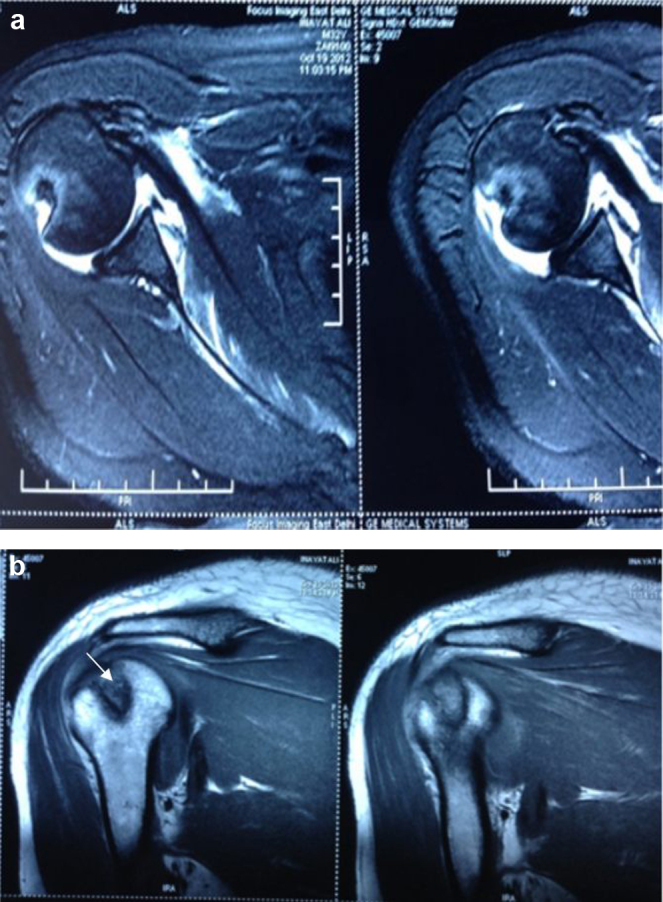

MR imaging revealed the Bankart's lesion and wedge shaped depression along the postero-lateral aspect of the humerus suggestive of Hill-Sach's lesion (Fig. 2a and b). Pre-operative CT scan showed Hill-Sach's lesion associated with coracoid process fracture (Fig. 3). Glenoid bony deficiency as measured on 3DCT scan was <25%, not considered as significant.

Fig. 2.

Magnetic resonance images (a) showing an anterior capsulo-labral tear (Bankart's lesion) and (b) wedge-shaped impaction (arrow) along the postero-lateral aspect of the humeral head (Hill-Sach's lesion).